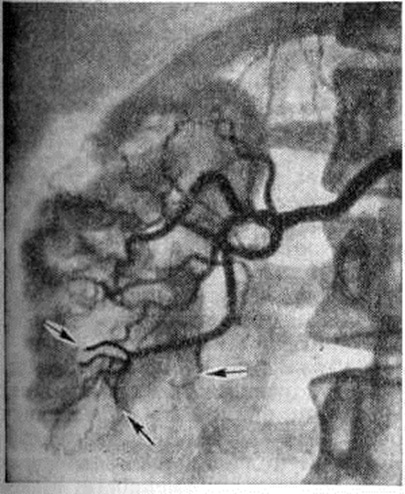

Гнойные очаги в верхнем полюсе почки приводят к ограничению подвижности диафрагмы, появлению выпота в плевральной полости, резкому ограничению подвижности поражённой почки (рисунок 1).

При почечной артериографии (смотри полный свод знаний Почечная ангиография) обнаруживают уменьшение калибра основного ствола почечной артерии по сравнению с артерией другой стороны. В начале заболевания наблюдается облитерация мелких сосудов коркового вещества почки, позже — более крупных сосудов, что придаёт ангиограмме вид обгорелого дерева. В нефрографической фазе исследования отчётливо видно изменение формы и размеров поражённой почки по сравнению со здоровой.

Радиоизотопная ренография, реография, почечная ангиография являются наиболее ценными диагностическими методами, позволяющими установить наличие Пиелонефрит и локализацию поражения (рисунок 3, 4).